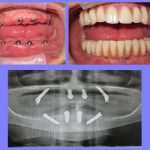

Dental Center Jurisic brings together a long family tradition, knowledge, experience and the constant education of its team to achieve the goal of oral health for its patients. There the patient is offered a complete palate of dental treatment such as basic dentistry (fillings and treatment), orthopantomographic x-ray system and complex implant, and prosthetic procedures in a comfortable and relaxing environment.

The center operates in cooperation with other leading experts to offer its patients the service of complete orthodontic care. Dental Center Jurisic offers all types of dental services some of which are:

Cosmetic dentistry ( porcelain veneers, metal-free ceramics, zirconium oxide, dental bleaching, fixed prosthetics, mobile prosthetics), implantology, periodontics ( classical and surgical method), surgery (root end resection, cystectomy, kir. Ex 8, levelling, pediatric dentistry) diagnostics and orthodontics (removable and fixed appliances).